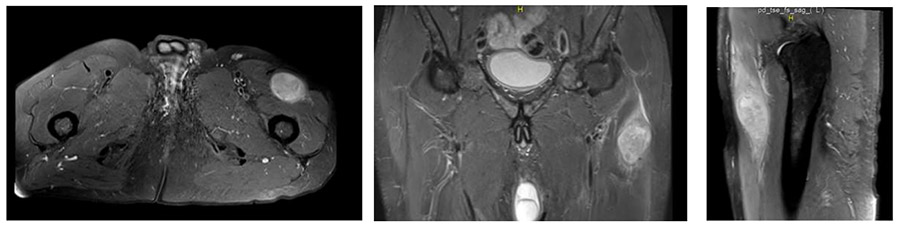

Ameliyat Öncesi: MR’da uyluk proksimal anterior yerleşimli düzensiz sınırlı, heterojen ve çevreleyen ödemin eşlik ettiği tümör kitlesi görülmekte.